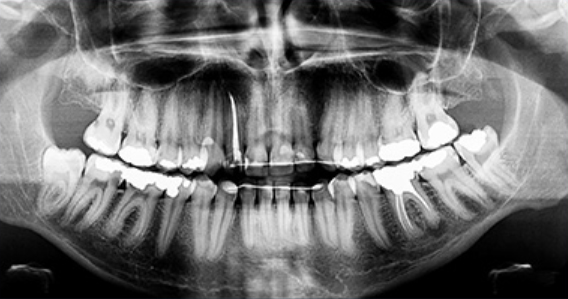

매복된 사랑니는 3D 첨단 CT촬영으로 상태를 정밀검사하고 발치계획을 세웁니다.

다양한 상태의 사랑니들을 다루어본 경험이 풍부하기 때문에 잇몸 속에

매복되어 보이지 않는 사랑니 발치가 가능합니다.

사랑니 발치 시에는 뿌리가 신경관과 근접해 있는지 또 어느쪽으로 휘어져 있는지를

파악해야 훨씬 더 안전하고 편하게

또 빠르게 뽑을 수 있습니다.

최첨단 3차원 CT를 이용하여 사랑니 뿌리의 위치와

신경관 위치 등을 정밀하게 분석한 후 시행하고 있습니다.